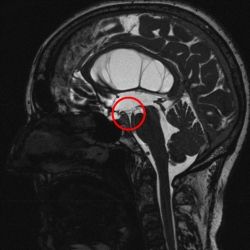

Prinzipiell stehen bei noch offener Fontanelle die Sonographie und die Kernspintomographie (MRT) zur Verfügung. Die Sonographie hat meist eine zu geringe Auflösung um zur Ursachendiagnostik eingesetzt zu werden. Die Computertomographie ist zur Ursachendiagnostik nicht sinnvoll, da der Informationsgehalt zu gering und die Strahlenbelastung für das kindliche Gehirn problematisch ist und vermieden werden soll. Somit ist die MRT die Untersuchung der Wahl. Da die diagnostische Präzision des MRT im Wesentlichen von der Qualität der Untersuchung abhängt, führen wir eine speziell auf die HIrnwasserräume abgestimmte hochauflösende Kernspintomographie, ggf. in Narkose, durch. Die Qualität dieser Aufnahmen unterscheidet sich erheblich von einer sog. „Standard-Kernspintomographie“. Mit diesem Vorgehen gelingt es häufig, zumindest eine erkennbare Ursache für einen Hydrocephalus darzustellen.

Ist die einzige Ursache des Hydrocephalus eine erworbene, umschriebene Abflussbehinderung des Hirnwassers im Bereich des sog. Aquädukt, der 4. Hirnkammer oder der Ausflussöffnung aus der 4. Hirnkammer, so kann diese Abflussbehinderung durch eine „innere Umleitung“ durch Eröffnung des Bodens des 3. Ventrikels umgangen werden.

Das hierfür verwendete Verfahren ist die endoskopische Ventrikulozisternostomie (englisch endoscopic third ventriculostomy = ETV). Hierbei wird ein feines Endoskop in die erweiterten Hirnkammern vorgeschoben und damit am Boden des 3. Ventrikels in einem Areal, welches keine Funktion enthält, unter Sicht meist mit einem Speziallaser eine Öffnung geschaffen.

Unter der Voraussetzung, dass das Hirnwasser aus den hier liegenden Hirnwasserräumen, den sogenannten „basalen Zisternen“, auch frei abfließen kann, und die o.g. Abflussbehinderung die einzige Ursache des Hydrocephalus darstellt, ist die ETV ein sehr elegantes und dann sehr erfolgreiches Verfahren.